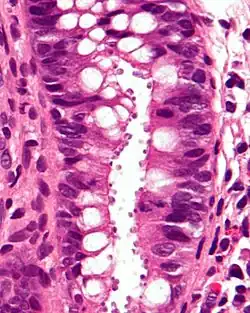

Bei der Kryptosporidiose handelt es sich um eine Durchfallerkrankung durch die zu den Apicomplexa gehörenden Kryptosporidien.

Die Betroffenen leiden unter wässrigen Durchfällen in Verbindung mit Bauchschmerzen und leichtem Fieber. Bei ansonsten Gesunden heilt die Erkrankung nach etwa einer Woche folgenlos aus, es entwickelt sich eine lebenslange Immunität. Bei Säuglingen und Immungeschwächten können jedoch längere und komplizierte Verläufe auftreten. Eine kausale Therapie steht derzeit nicht zur Verfügung. Bei Menschen mit zellulärer Immunschwäche (z. B. AIDS) tritt diese sonst seltene Erkrankung gehäuft auf. Hier ist neben der symptomatischen Behandlung eine Optimierung des Immunstatus durch antiretrovirale Therapie vordringlich.

Neunzehn verschiedene Arten von Kryptosporidien sind bisher beim Menschen nachgewiesen worden. Zu 95 % sind die Erreger jedoch Cryptosporidium hominis oder Cryptosporidium parvum, gefolgt von Cryptosporidium meleagridis, Cryptosporidium felis sowie Cryptosporidium canis.[1]

Die Oozysten können mit Hilfe von diversen Färbeverfahren (z. B. modifizierte Ziehl-Neelsen-Färbung) in Stuhlausstrichen nachgewiesen werden. Außerdem ist ein Nachweis durch Immunfluoreszenz, oder Kopro-Antigen-Nachweis via ELISA möglich.